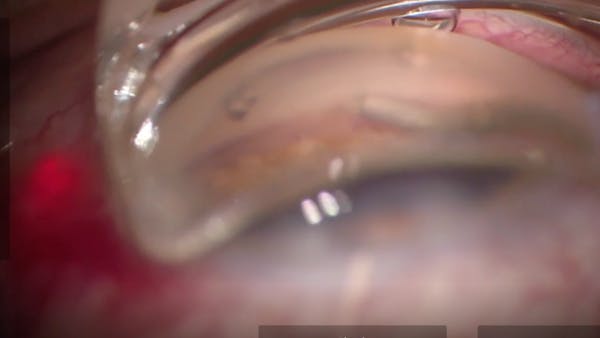

I. Paul Singh, MD

Inder Paul Singh, MD